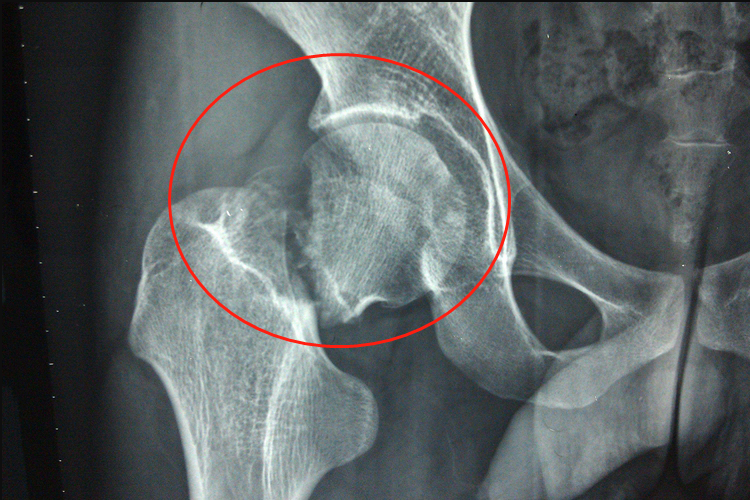

嵌插骨折表现为长管状骨的干骺端发生骨折片相互嵌插,骨密质插入松质骨内。

嵌插骨折表现为长管状骨的干骺端皮质骨与骨松质交界处,发生骨折片相互嵌插,骨密质插入松质骨内,伴伤处肿胀疼痛,有活动障碍。